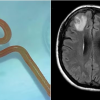

Unutkanlık ve depresyon şikayeti ile hastaneye giden kadının beyninde 8 santim uzunluğunda can solucan bulundu.

64 yaşındaki hastanın beyninde yapılan manyetik rezonans görüntüleme (MRG) taraması, ameliyat gerektiren anormalliklerin olduğunu gösterdi. Ancak nörocerrah Bandi, bu tür bir durumu hiç beklemiyordu. "Nörocerrahlar sık sık beyindeki enfeksiyonlarla uğraşırlar, ancak bunun bir solucan olacağını düşünmek bile akıllarına gelmezdi," dedi.